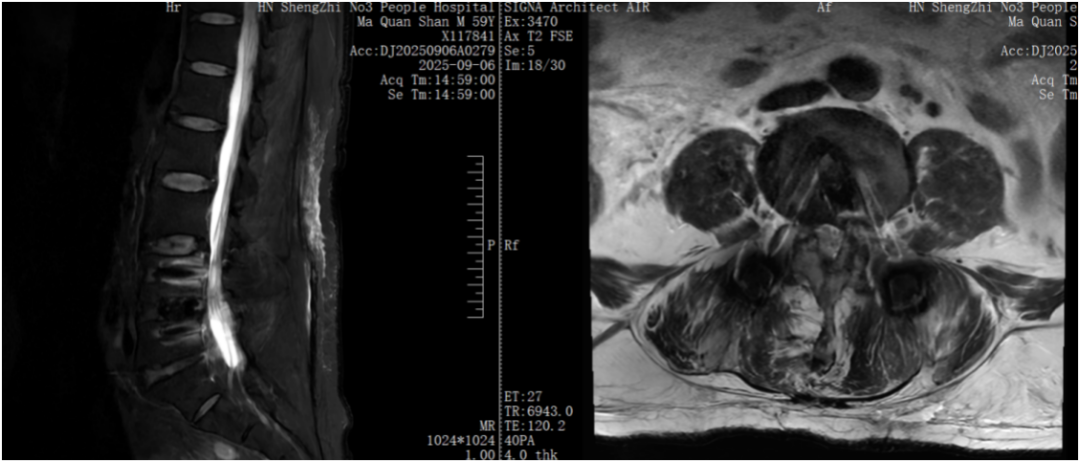

原来啊,在 20 年前他因腰椎问题接受了腰 5 骶 1 开放手术,但随后他的腰 4/5 节段出现不稳,腰部疼痛逐渐加剧,并伴有左下肢麻木、发凉,到了最近,他连日常行走站立都变得异常困难。

贺毅团队一致认为,传统开放手术风险过高,不适合马叔叔的情况。经过反复讨论,最终为他制定了内镜下腰 4/5 椎管减压+腰椎间盘切除+椎间植骨融合内固定术的微创手术方案。

手术过程很顺利,术后马叔叔腰部疼痛和左下肢麻木、发凉的症状明显缓解。

如今,马叔叔的恢复情况良好,不仅生活能够自理,还能按时前往医院进行透析治疗。他的案例也证明,对于像他这样有多次手术史、基础疾病多、对开放手术恐惧的患者,腰椎微创手术是不错的治疗选择。即使既往做过腰椎开放手术等其他治疗,如果需要再次手术,也可以根据病情选择合适的微创手术方法解决患者的痛苦。